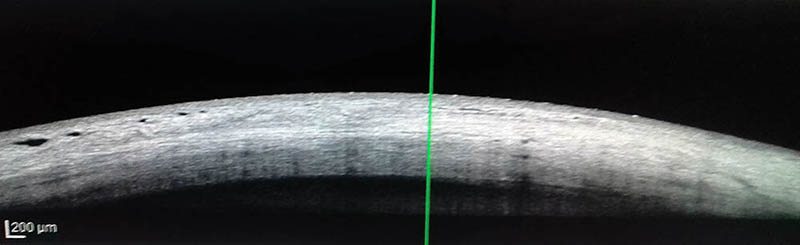

Figura 1:

Esclera normal que presenta 3 áreas diferentes de reflectividad y observación de vasos colectores.

Evaluaciones preoperatorias: agudeza visual, biomicroscopía del segmento anterior y posterior, espesor de la capa de fibras de la papila (OCT Spectralis), características de la esclera normal y pacientes, con hipotonía persistente, con OCT Spectralis). La esclera normal se caracteriza por poseer tres capas de diferente reflectividad por atenuación del paso de la luz láser y las áreas hiporreflectivas con sombras corresponden a vasos conjuntivales y epiesclerales y esclerales profundos y medios, que suelen dar sombras reflectivas, no así los intraesclerales superficiales o profundos. Mastropascua 23 considera áreas hiporreflectivas aquellas que son menores del 50% del promedio de intensidad de reflectividad de las tres capas normales o que estén alrededor con patrón normal. El campo visual computado (Octopus G1X TOP - progresión y estadificación del daño glaucomatoso). Se descartaron causas de hipotonía: desprendimiento cilio-coroideo persistente y Seidel+ (biomicroscopía anterior y posterior, UBM, ECO B). A todos los pacientes con hipotonía persistente con presiones de 2 ± 1 mmHg, que recibieron tratamiento y seguimiento durante 13 +- 7 meses, rango: de 3 a 52 meses se les colocó tempranamente, en algunos pacientes, (60 días postoperatorio), lente de contacto de 16 mm, sangre autóloga y suturas de compresión de la ampolla (Palmberg). Posteriormente se realizó plástica de la ampolla y colocación de parche escleral, tampoco hallando resultados positivos, aumentando la PIO. Por último vitrectomía con C3F8 o SF6.